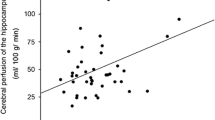

Vagal baroreflex sensitivity (BRS-V) was reduced in a significantly larger proportion of participants with psychosis compared with patients with nonpsychotic affective disorders, whereas participants with psychosis had increased adrenergic baroreflex sensitivity (BRS-A) compared with participants with no history of psychiatric disease. Only in psychotic cases were baroreflex sensitivities associated with hippocampal metabolite concentrations. Specifically, BRS-V was inversely correlated with myo-inositol, a marker of gliosis, and BRS-A was positively correlated with energy dependent dysmyelination (choline, creatine) and excitatory activity (GLX).

Laosiripisan J et al (2015) Association between cardiovagal baroreflex sensitivity and baseline cerebral perfusion of the hippocampus. Clin Auton Res 25(4):213–218. https://doi.org/10.1007/s10286-015-0296-8